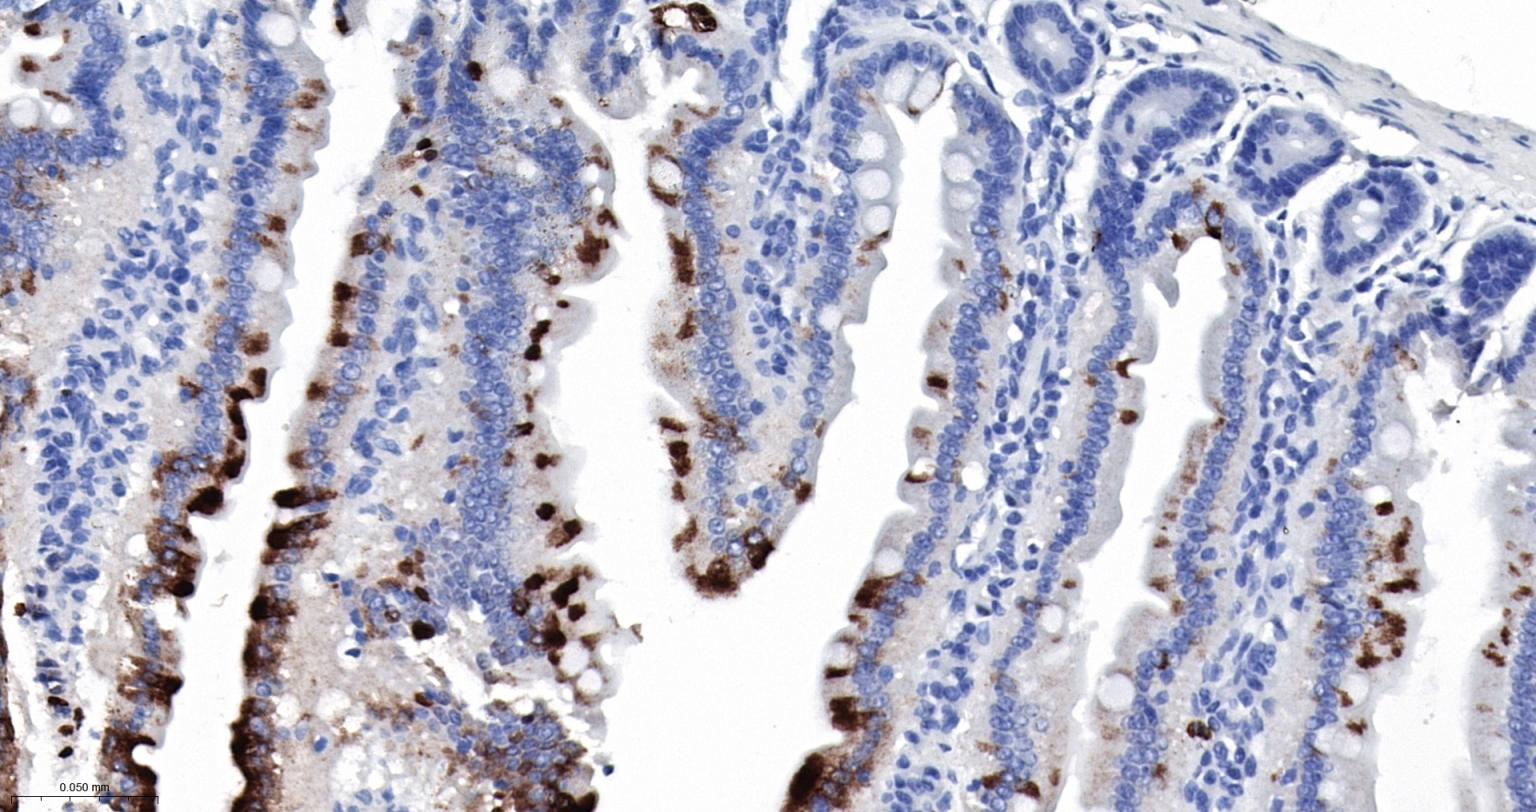

Paraformaldehyde-fixed, paraffin embedded Rat Small Intestine; Antigen retrieval by boiling in sodium citrate buffer (pH6.0) for 15 min; The section was incubated with S100A8 Monoclonal Antibody, Unconjugated (bsm-61167R) at 1:200 overnight at 4°C, followed by conjugation to the bs-0295G-HRP and DAB (C-0010) staining.